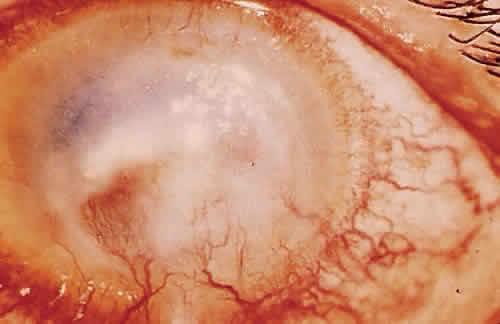

Cell-mediated immunity also plays an important role locally and systemically in the eye's defense against microorganisms. When a T lymphocyte becomes sensitized to a bacterial antigen, it releases a soluble factor (lymphokine) that can invest the macrophage with the power to destroy ingested organisms. The sensitized T lymphocyte also releases factors that can aggregate macrophages at the site of insult and hinder their departure from the site. Chemotactic factors for neutrophils, basophils, and eosinophils are also released.2 The leukocyte infiltrate may confine the pathogen and prevent its entrance into the interior of the eye, but may also contribute to the necrotizing inflammation of the corneal stroma seen in gram-negative bacteria and herpes simplex virus (HSV).20